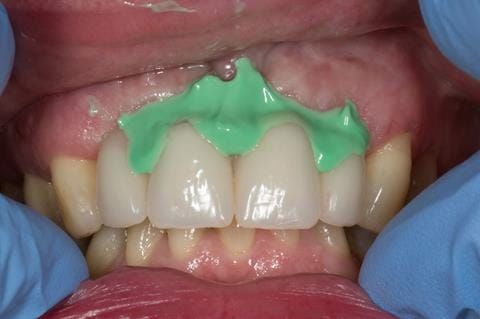

- Extract the upper 2-2 teeth and replace with an interim acrylic based partial denture. Reline the interim denture over 9 - 12 months, replacing with a definitive cobalt chromium based partial denture. The definitive denture would ideally be designed as an occlusal protective splint to reduce the the potential for mechanical wear and breakages of the moderately/heavily restored maxillary dentition. In addition, should further upper teeth require extraction they could be added on to the denture cobalt chromium framework - therefore a new prosthesis would not be required as future teeth are lost. This option would produce an excellent aesthetic outcome. This is the option the patient chose to have.

Following consultation and second discussion appointment the patient chose to have option 3 namely, a maxillary cobalt chromium based partial denture/protective occlusal splint. The clinical situation and treatment process is shown in detail below with photographs. The patient was successfully rehabilitated with this and her quality of life considerably improved. The clinical work was provided by Finlay and the technical work by Rowan.